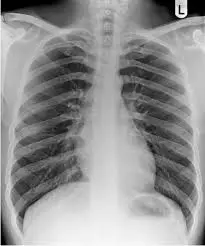

Quais os achados radiológicos mais comuns na pneumonia comunitária?

Infiltrado pulmonar do tipo alveolar broncopneumônico com presença de broncograma aéreo